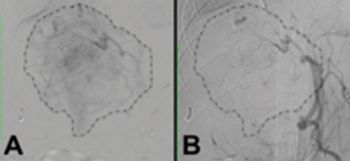

When you have a patient with a hepatic vascular abnormality, how do you confirm it?

Add a little contrast to help you find your diagnosis.